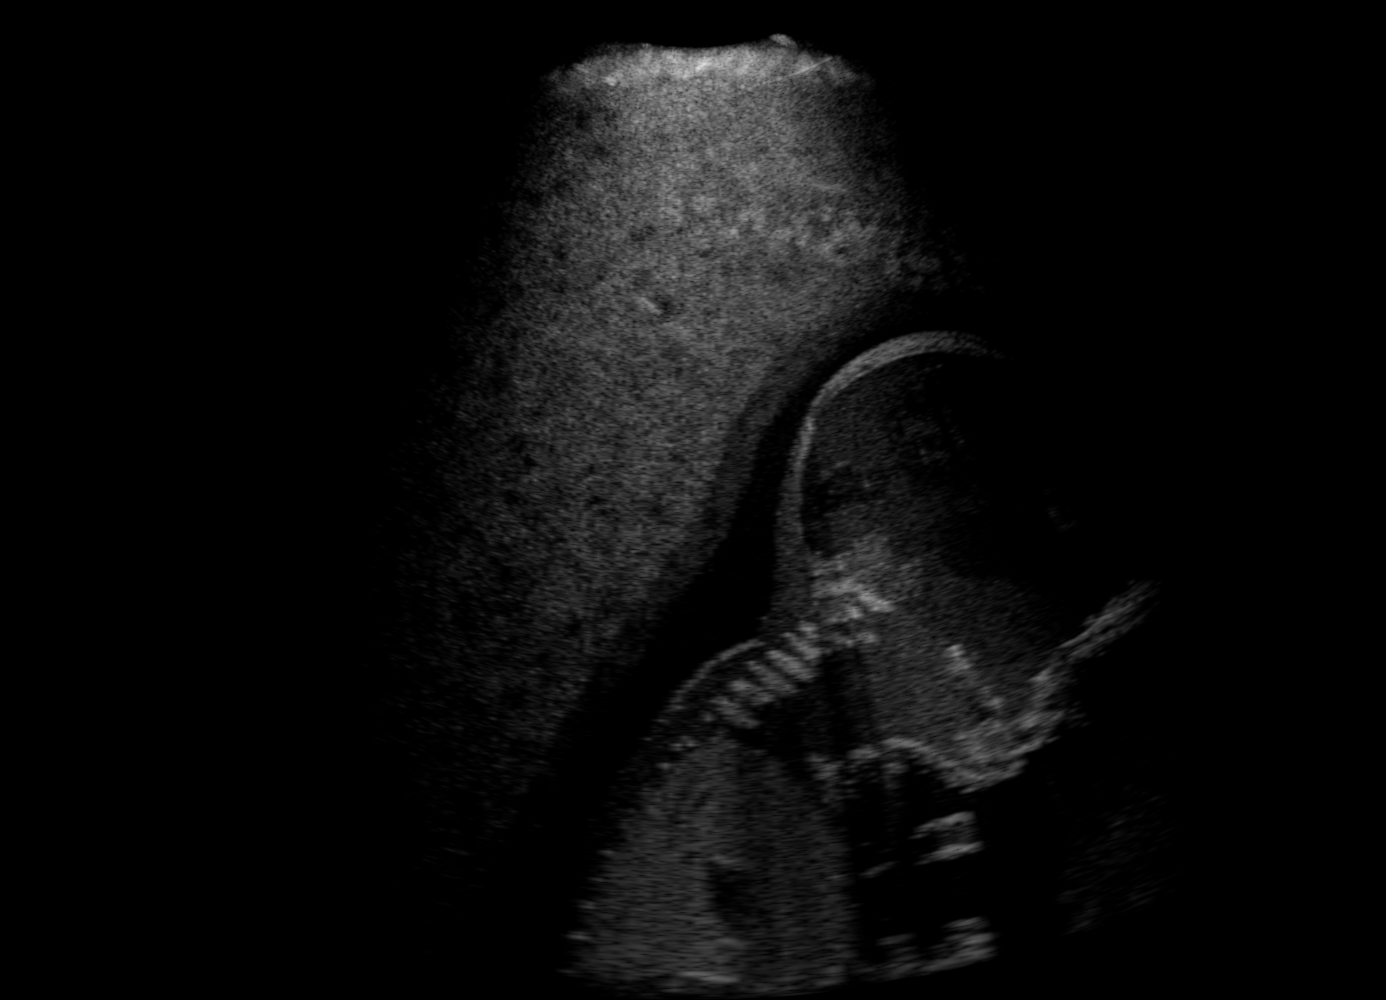

US images. For each regularly-sampled key frame of a simulated US fetal exam, paired low and high quality images are generated using two simulation passes: low quality images using one primary ray per US scanline and one elevational layer; and high quality images using 32 primary rays per scanline and three elevational layers [10]. Other simulation parameters are kept identical for both simulation passes, cf Table 1. Example B-mode images are shown in Fig. 1(a-b).

Qualitative Results. Fig. 3 shows a visual comparison of the three model variants on four examples. The baseline L2HM fails to preserve anatomical structures due to missing structural information in the input images. Resulting ambiguities in the network prediction cause artifacts such as blur in regions that feature fine details such as bones. Providing segmentation maps as additional input (L2HMS) greatly reduces such artifacts as shown in Fig. 3(c). However, L2HMS still struggles in modeling complex non-local features such as directional occlusion artifacts, note the lack of acoustic shadows in Fig. 3(c). In contrast, our final model L2HMSA is able to accurately synthesize these features and produces translations significantly closer to the target, as demonstrated in Fig. 3(d). In particular, our proposed model with segmentation and attenuation integral maps is able to recover both missing anatomical structures and directional artefacts.

Above image translation has been demonstrated on patches. For the entire field-of-view (FoV) US images, patch fusion from image translation of non-overlapping patches would cause artifacts at image seams. Averaging overlapping patches, on the other hand, would blur the essential US texture. Although seamless tiling of US images is possible using graphical models [3], this requires prohibitively long computation time. Herein, we instead directly apply our trained generator on full FoV low-quality images, since the generator is fully convolutional and thus can operate on images of arbitrary size. Fig. 4 shows two examples of translated images by L2HMS and L2HMSA, demonstrating direct inference on full FoV images. While anatomical structures are well preserved and the effect of attenuation integral map is apparent, speckle texture appearance is seen to degrade slightly especially in the top image regions, where the ultrasound texture looking particularly different due to focusing difference and near-field effects.

(a) Input

(b) L2HM

(c) L2HMS

(d) L2HMSA

(e) Target